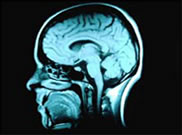

Brain Injury Case Management

Brain injury case management can mean having to deal with some complex issues. This is why it is advisable to always choose a case management team that has experience with this type of injury. Rehabilitation from a catastrophic brain injury can take a lot of work and involve dealing with a large number of different professionals and services means that any case manager will really need to be up to speed. The good news is that utilising brain injury case management can make a huge difference by ensuring that things move faster and more effectively. More and more clients and their families are becoming convinced of the need for this type of service – chances are that if you try it you will be convinced too.

A brain injury is one of the most difficult injuries to recover from- a large number of people will never be able to fully return to how things were before their accident. For some people the brain injury might leave a lasting physical disability while for others it could mean a permanent change to their personality. Rehabilitation can make a huge difference though and this is why you want to be sure that you are getting the best possible assistance Here are just some of the ways that brain injury case management can help during the rehabilitation process.